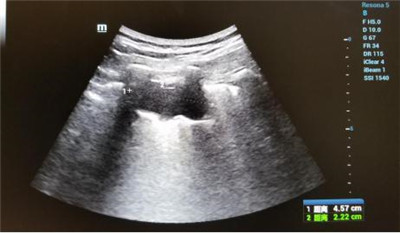

患者郑女士,在MILAN.COM被确诊肺癌,癌肿位于左肺下叶近胸膜处,大小约4.5x2.2cm,经化疗后肿块变化不明显。肿瘤外科二病区王雅辉副主任医师与超声科刘晓晖主任医师会诊后,认为可以为患者施行超声引导下肺癌微波消融术,因为属于首例,特邀西京医院王建宏教授进行术中指导,超声科华玺主治医师进行引导,麻醉手术科李万鹏副主任进行术中监测,降低手术风险,提高肿瘤综合治疗效果。整个治疗过程约30分钟,患者术中术后生命体征平稳。